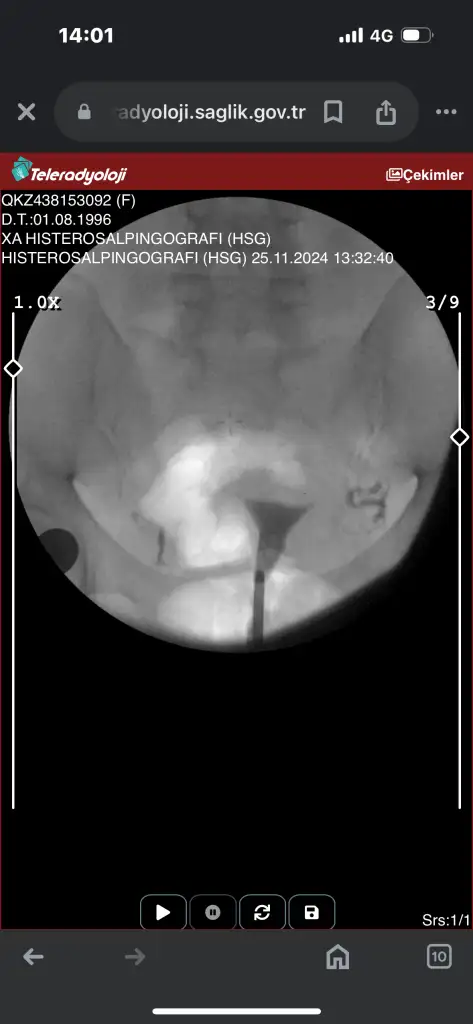

Canım tek tüpün kapalı galibaKızlar acil sonucuma bakarmısınızz ben hiçbirşey anlamıormm